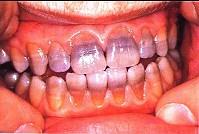

问题 关于四环素牙,下列哪—项错误 ( )

选项 A.四环素可通过胎盘引起乳牙着色 B.四环素对牙的影响仅仅是着色,影响美观 C.通常前牙比后牙着色深 D.四环素在牙本质中的沉积比在釉质中高4倍 E.四环素牙的着色是永久的

答案 B